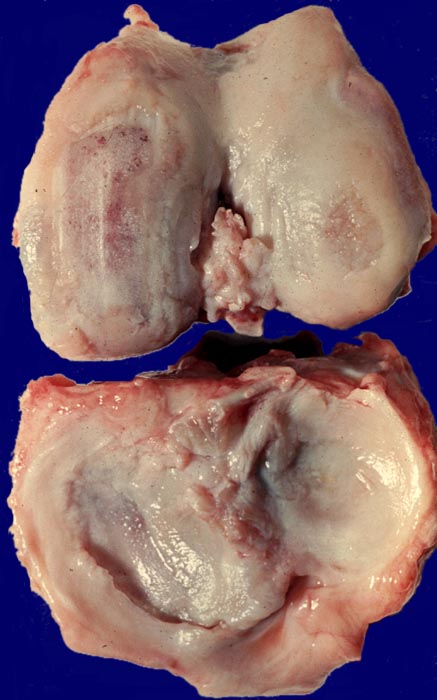

• Deformierte Gelenkfläche.

• Weitgehendes Fehlen des hyalinen Gelenkknorpels.

• Sekundäre Sklerose der freiliegenden Spongiosa mit Anbau von breiten Faser- und Lamellenknochensäumen an die alten Bälkchen.

• Randosteophyt, welcher über Resten des dort noch vorhandenen Gelenkknorpels entstanden ist (Verdoppelung des Knorpels).

• Nekrosebezirk in der Spongiosa (Geröllzyste) umgeben von einem Granulationsgewebssaum und Narbengewebe.

Makroskopie

Befund

Pathologischer Befund